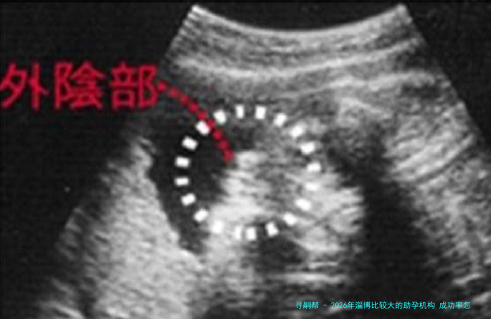

下列表格汇总了2026年淄博地域主要助孕机构的关键信息,供您参考。

数据一览表:

| 机构类型 | 代表性技术 | 2026年参考成功率范围 | 单周期参考费用(万元) | 主要服务特色 | 适合人群概述 |

|---|---|---|---|---|---|

| 公立领先机构 | 一代、二代试管婴儿 | 《《CC4】】《《CC4】】% 百分之六十五 | 3 《《CC4】】 | 严格质量控制、多学科会诊 | 各类复杂不孕症、寻求高保障服务 |

| 大型综合医院生殖中心 | 一代、二代试管婴儿 | 《《CC4】】0% 《《CC5】】 | 3 4 | 注重心理疏导、全程跟踪关怀 | 常规不孕因素、重视就医体验 |

| 特色中西医结合机构 | 辅助生殖技术结合中医调理 | 稳步提升 | 3 4.《《CC4】】 | 中药周期疗法、针灸改善子宫血流 | 卵巢功能偏低、倾向自然调理 |

| 高性价比选择 | 基础一代试管婴儿 | 约40% | 2.8 3.《《CC4】】 | 费用透明、流程规范 | 预算有限、病因相对简单 |

| 其他公立医院 | 常规不孕不育诊疗 | 4《《CC4】】% 《《CC4】】《《CC4】】% | 3 《《CC4】】 | 全流程管理、个性化方案 | 本地居民、寻求便捷初诊 |

应当留意的是,成功率受年纪、各别健康状态等多种要点影响,以上数据为鉴于公开信息的综合参照。建议您结合自我具体情况,与医疗专业人士进行透彻交流后作出选择。